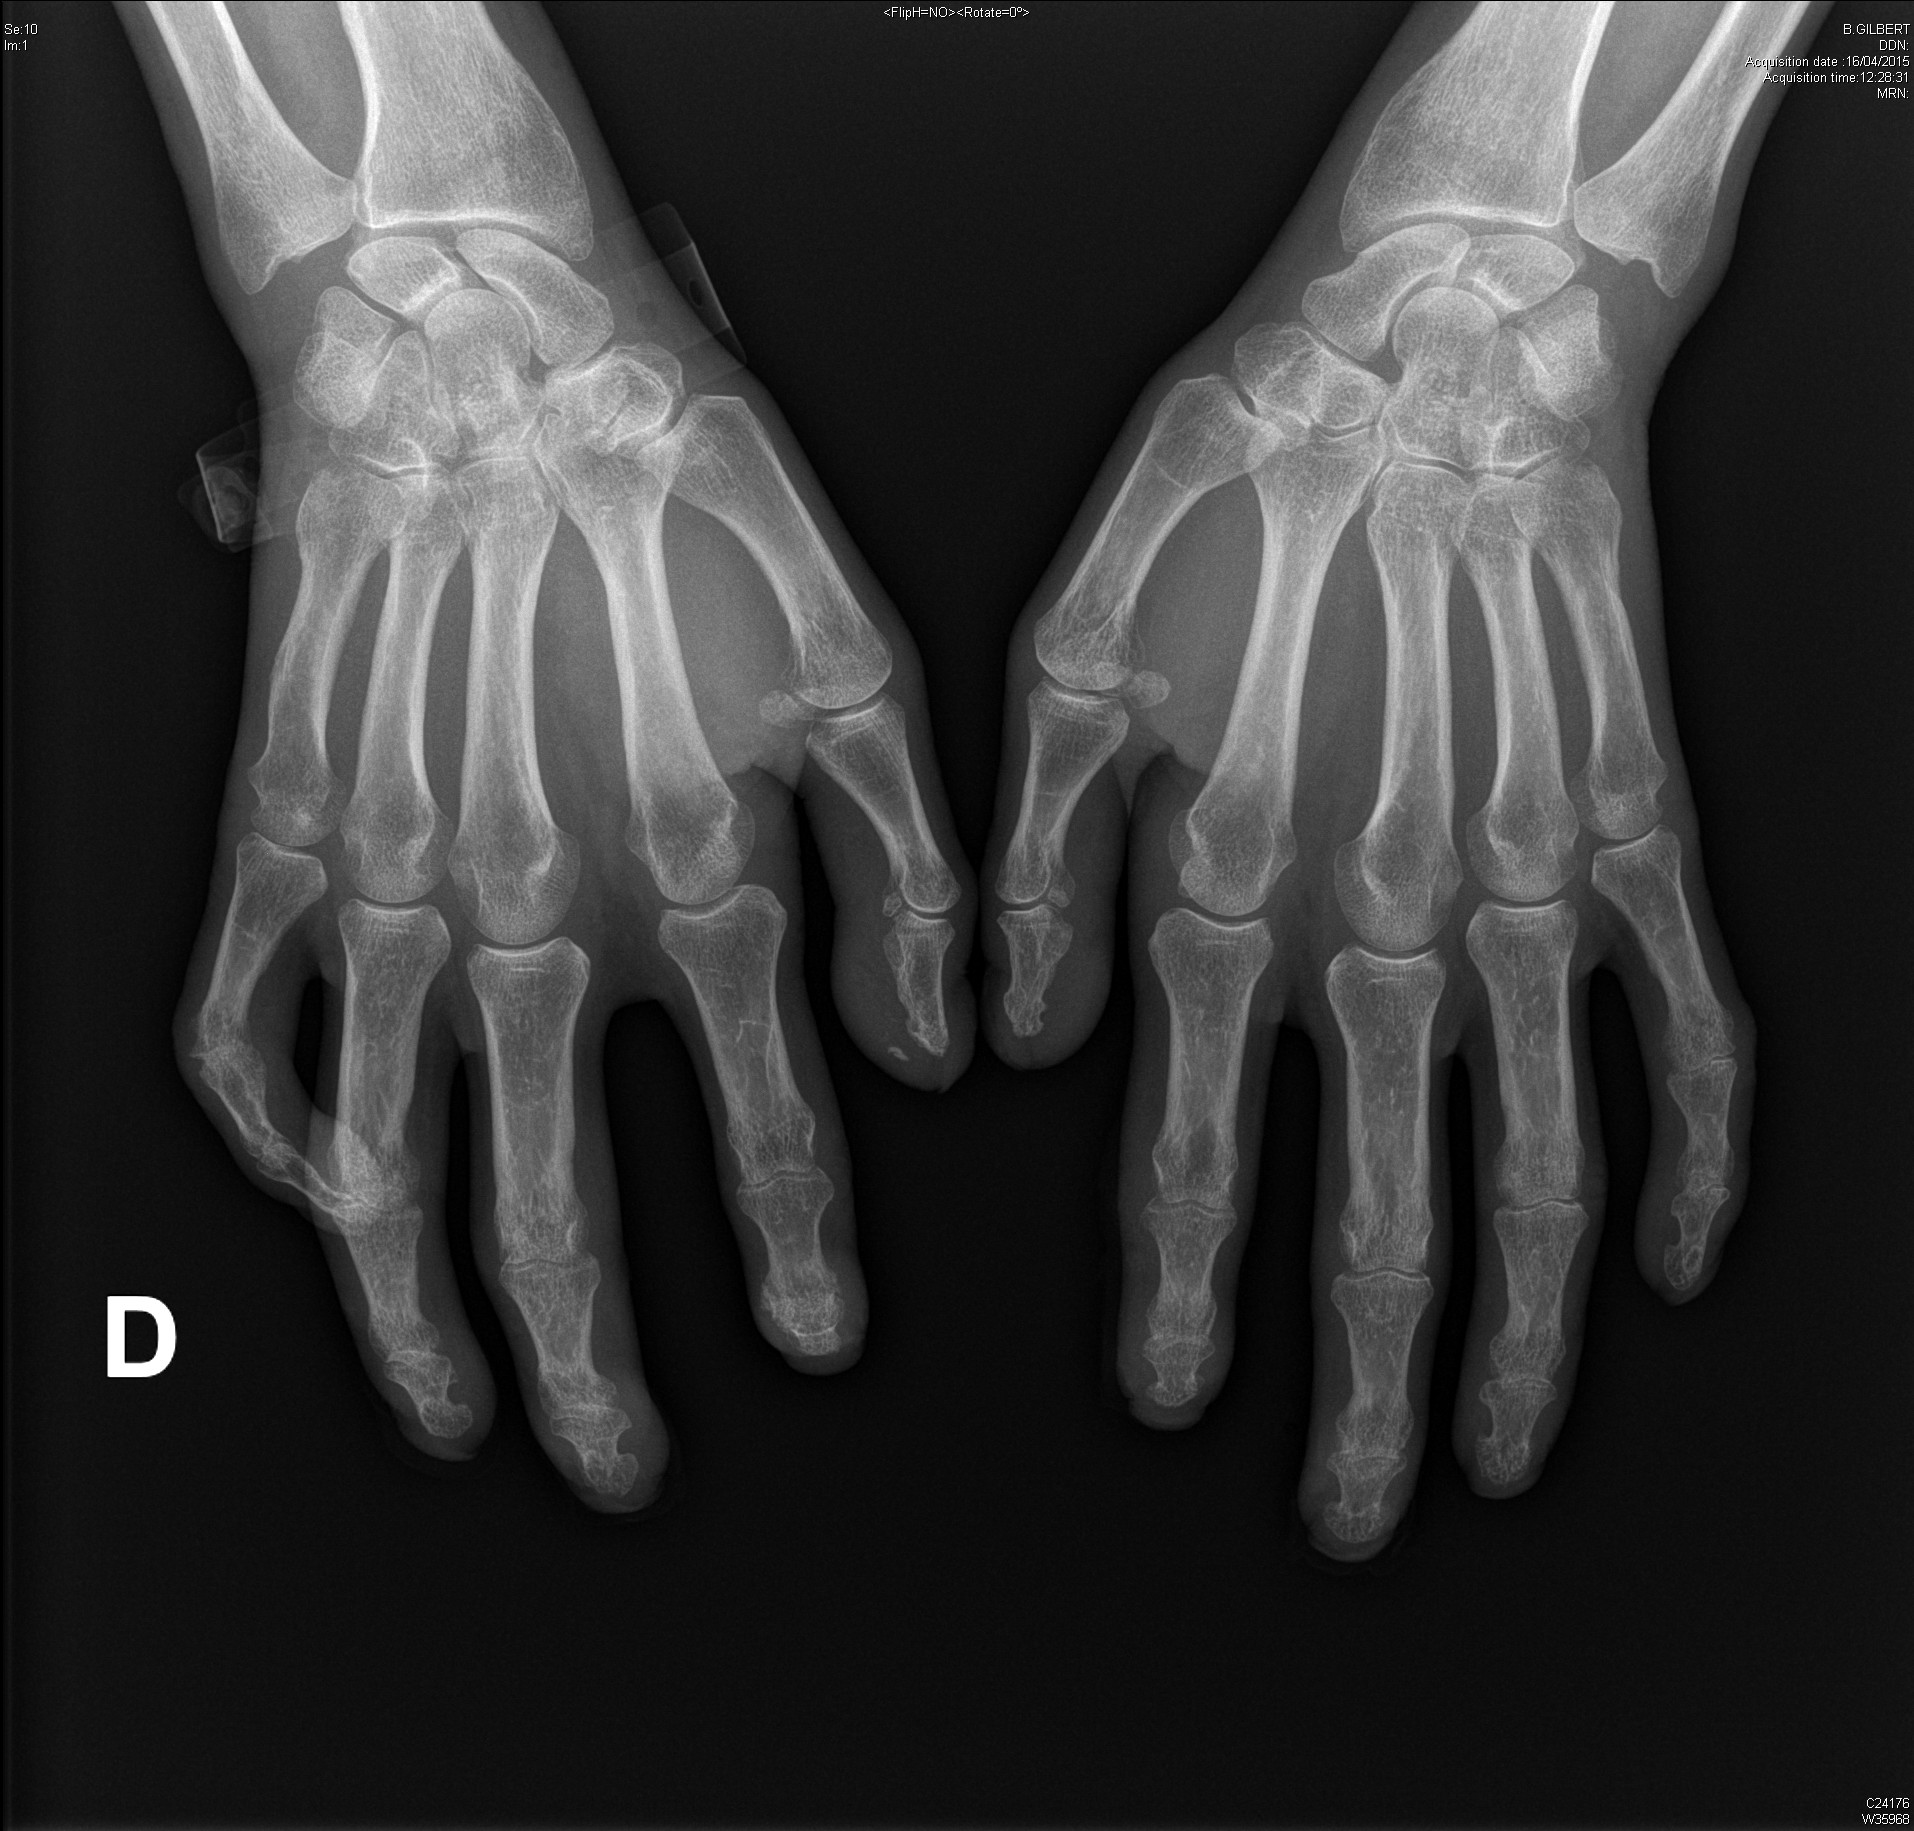

Carpite bilatérale évoluée dans le cadre d'une polyarthrite rhumatoïde